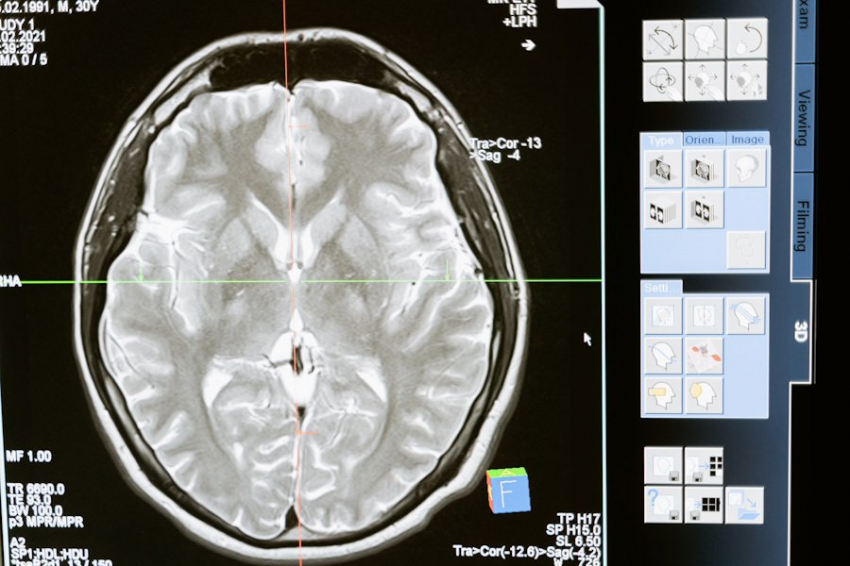

Это были люди, в основном, после тяжелых травм мозга. Их просили представить, что они сжимают и разжимают ладонь. При помощи функциональной магнитно-резонансной томографии и электроэнцефалографии ученые отслеживали реакции мозга в моменты выполнения заданий и в покое.

Выяснилось, что, минимум, у 25% испытуемых в ответ на призывы специалистов в течение нескольких минут фиксировалась заметная активность мозга. Причем, конкретно в тех зонах мозга, что ответственны за действия, которые им предлагались. Получается, что люди «в вегетативном состоянии» услышали и поняли обращения ученых, более того, прилагали усилия, чтобы их исполнить.